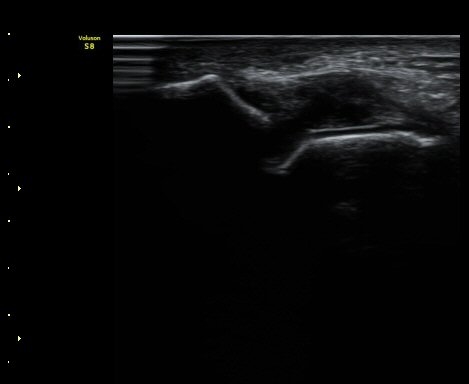

¹ß¸ñ°üÀý ¾Õ Á¾´Ü¸é°Ë»ç¿¡¼­ ¼Ò·®ÀÇ ¼ö¾×Àú·ù°¡ °üÂûµÈ´Ù(±×¸² 1, 2).